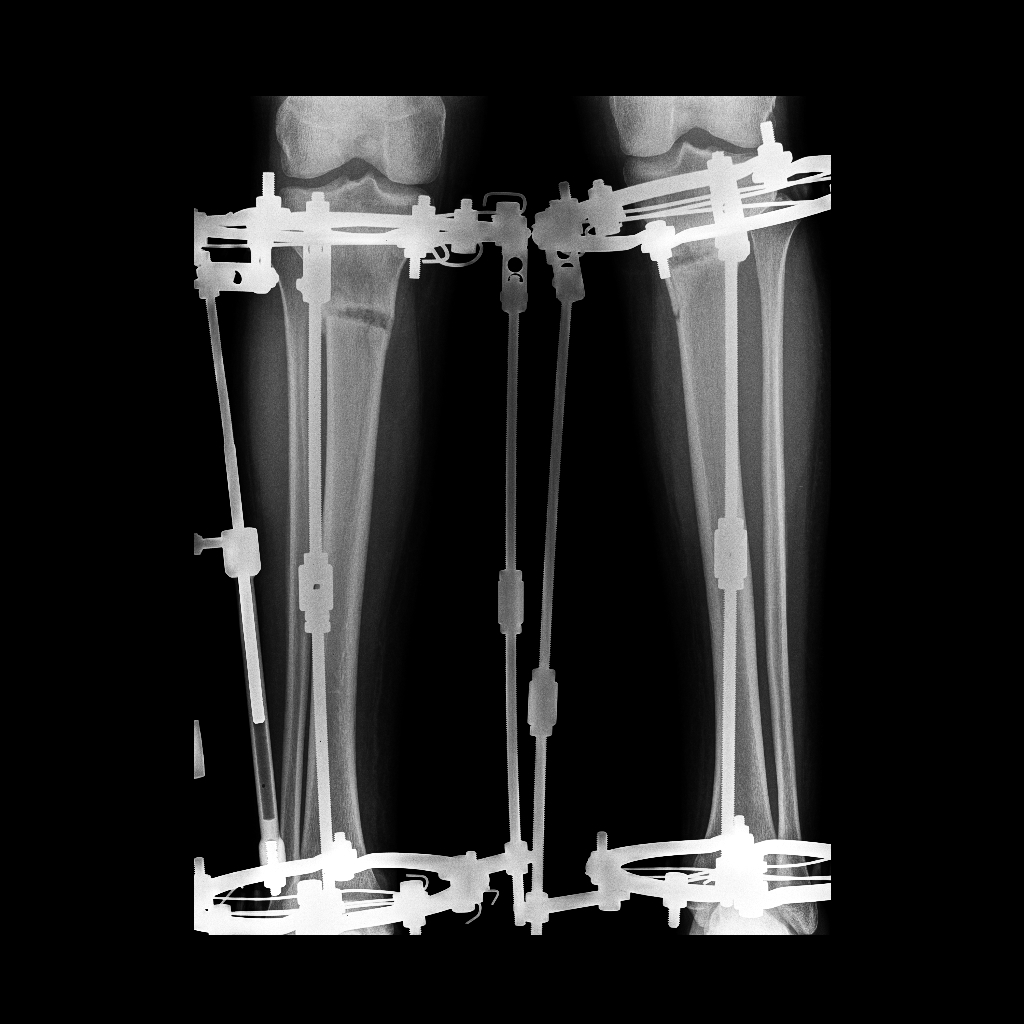

Исходник - 26 лет.

Дата операции 27.09.2016г.